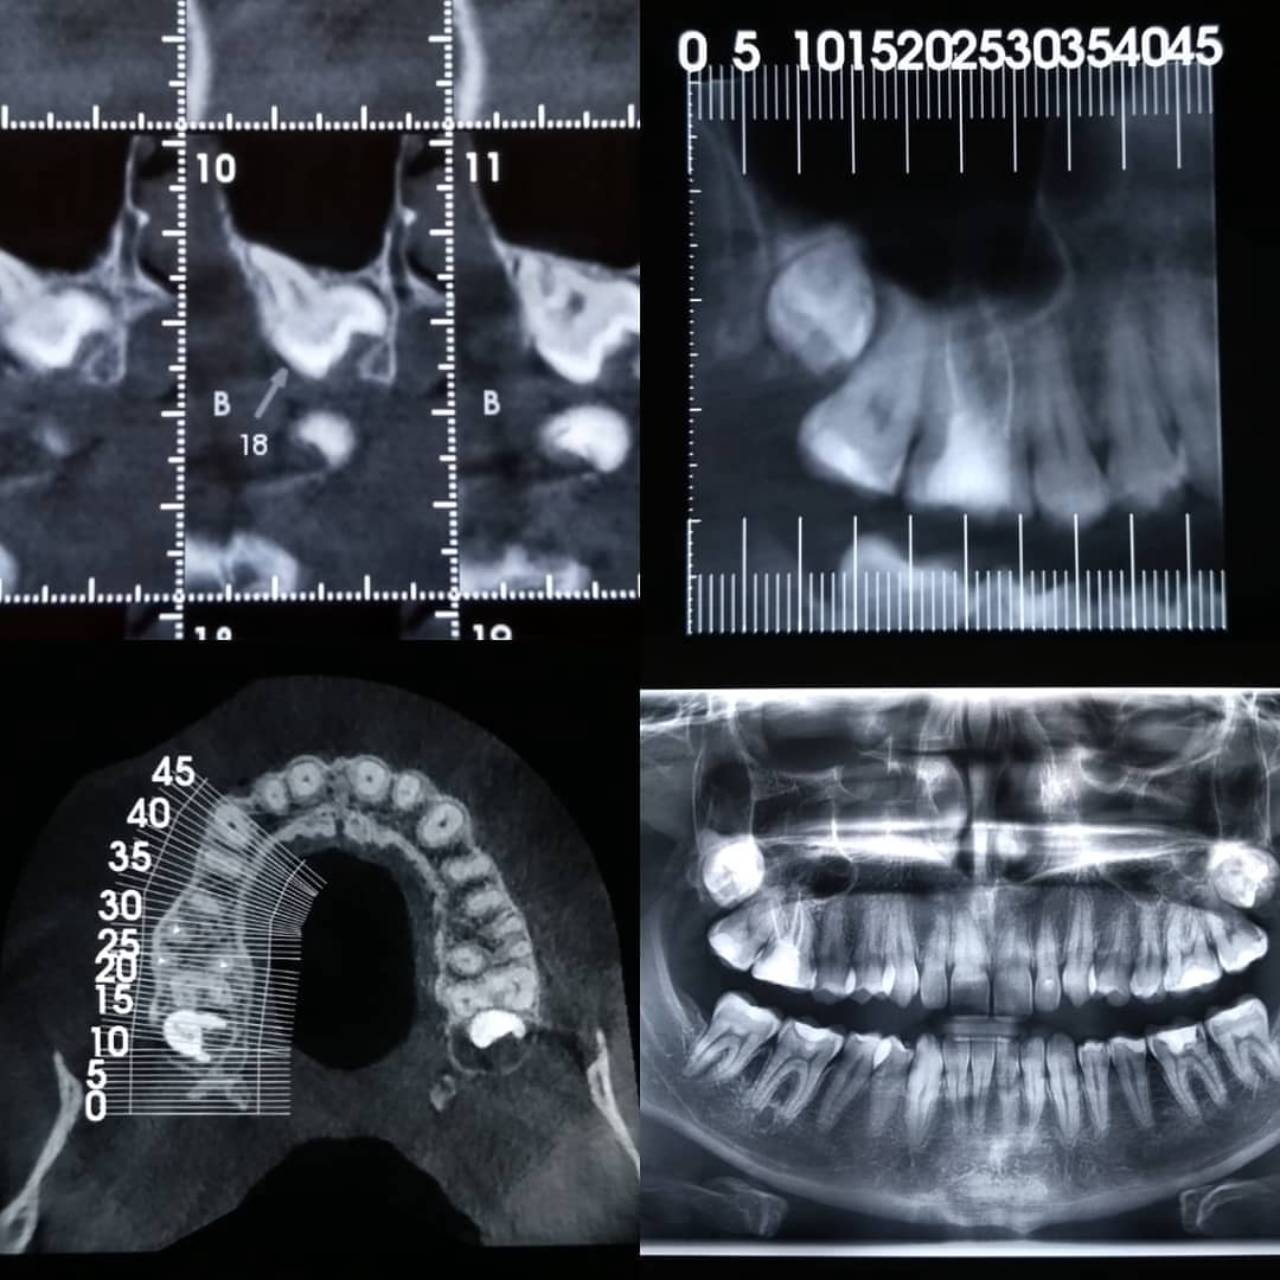

Tomografia Segmentada

- Dente incluso / Supranumerário

- Fratura óssea

- Fratura / Trepanação / Dilaceração Radicular

- Reabsorção Radicular

- Espessura das Tábuas Ósseas V e L

- Avaliação do tratamento Endodôntico

- Área patológica

Tomografia Computadorizada